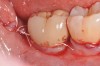

At 1 year following treatment, probing depths are now 3 mm with an absence of bleeding.

Figure 6

Figure 7